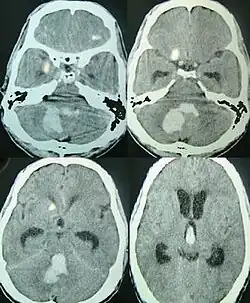

CT scan of a spontaneous intracerebral bleed, leaking into the lateral ventricles | |

Intraparenchymal hemorrhage can be recognized on CT scans because blood appears brighter than other tissue and is separated from the inner table of the skull by brain tissue. The tissue surrounding a bleed is often less dense than the rest of the brain because of edema, and therefore shows up darker on the CT scan.[31] The oedema surrounding the haemorrhage would rapidly increase in size in the first 48 hours, and reached its maximum extent at day 14. The bigger the size of the haematoma, the larger its surrounding oedema.[32] Brain oedema formation is due to the breakdown of red blood cells, where haemoglobin and other contents of red blood cells are released. The release of these red blood cells contents causes toxic effect on the brain and causes brain oedema. Besides, the breaking down of blood-brain barrier also contributes to the odema formation.[13]